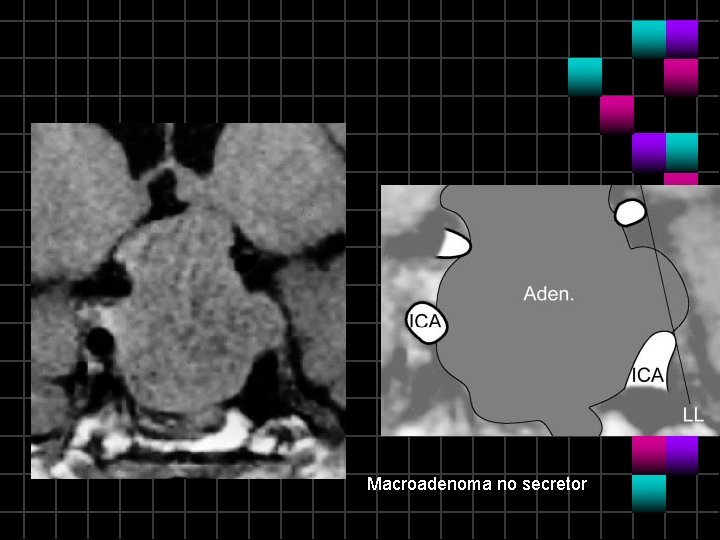

Macroadenoma no secretor

Macroadenoam no secretor Invasión del 42%